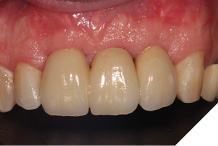

The definitive bridge was fitted and torqued in situ uneventfully after such excellent healing of the provisional bridge (Figs. 31-37).

Fig. 33

Fig. 34